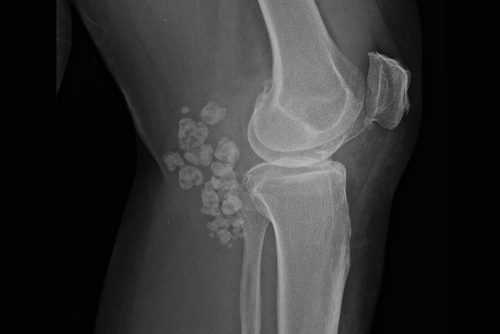

Чаще всего рентген назначают при подозрении на вывих, растяжение, перелом, разрыв сухожилий и другие травмы. Однако это исследование позволяет также увидеть изменения в структуре тканей, обнаружить опухоли, кисты, деформации, артроз и артрит. Поэтому диагностический метод эффективен при любых жалобах в отношении опорно-двигательного аппарата.

Рентгеновский снимок позволяет исследовать деформации, наличие остеофитов (отложение солей), трещины, инородные тела, состояние мягких тканей при первичной диагностике.